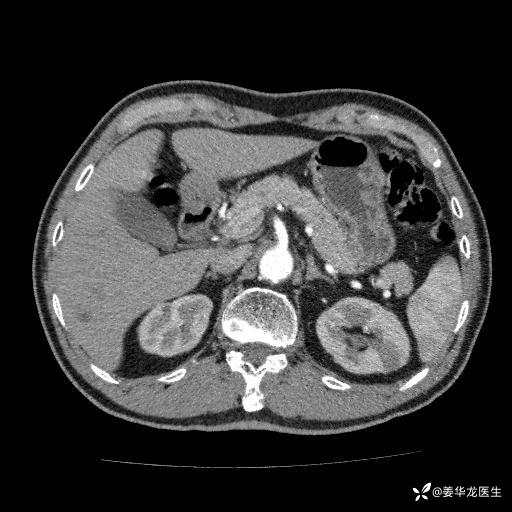

左肾中心型肾门部肿瘤39mm×34mm×36mm,右肾GFR25ml/min,部分切还是全切?

患者75岁老年男性,体重50kg,无高血压、肾病、糖尿病等基础病,检查发现左肾中心型肾门部肿瘤,右肾GFR只有25ml,无肉眼血尿,无镜下血尿。入院验血常规检查均正常,包括肾功能,肌酐102.7umol/L.

二、左肾肿瘤与左肾集合系、左肾动静脉关系密切,左肾部分切除术可行吗?成功率有多大?成功部分切后,肾功能还有多少?